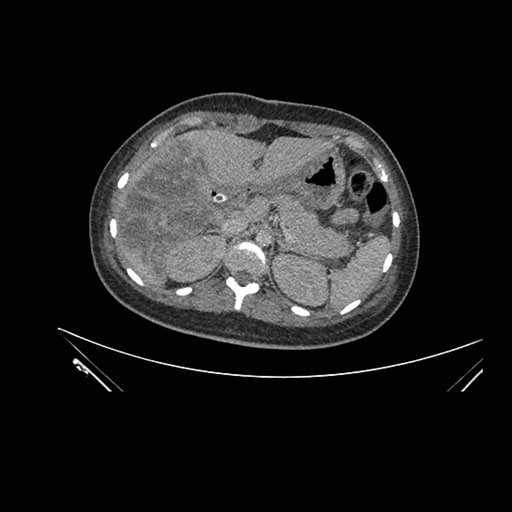

Imaging Analysis

Look through the patient's CT scan to identify any areas of concern for the necessary procedure.

Coronal Venous

Based on initial findings, which issue(s) would you be most concerned about?